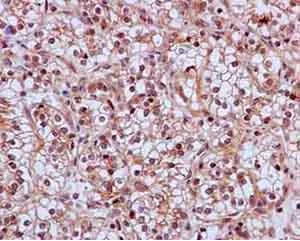

Immunohistochemistry (Formalin/PFA-fixed paraffin-embedded sections) - Anti-SKP2 antibody [EPR3305(2)] - BSA and Azide free (AB240263)

immunohistochemical analysis of paraffin embedded Human kidney clear cell carcinoma tissue labeling SKP2 with ab183039 at 1/50 followed by secondary staining with Ready to use HRP Polymer for Rabbit IgG and counterstained with Hematoxylin.

This data was developed using the same antibody clone in a different buffer formulation containing PBS, BSA, glycerol, and sodium azide (ab183039).

Perform heat mediated antigen retrieval with EDTA buffer pH 9 before commencing with IHC staining protocol.